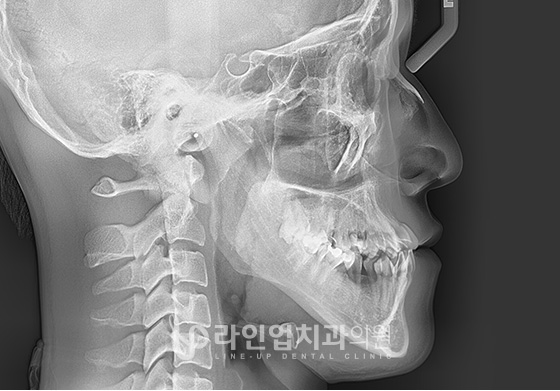

전후사진

치료후 After